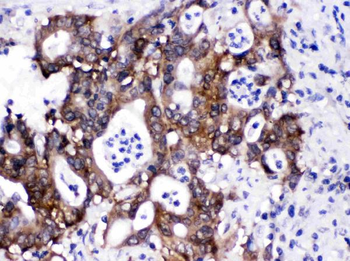

−| Tested Applications | ELISA, IHC |

| Dilution Range | IHC-P:1:20-1:200 |

| Immunogen | Recombinant Human Protein S100-A6 protein (1-90AA) |

| Target | S100A6 |

S100A6 Antibody (orb239280)